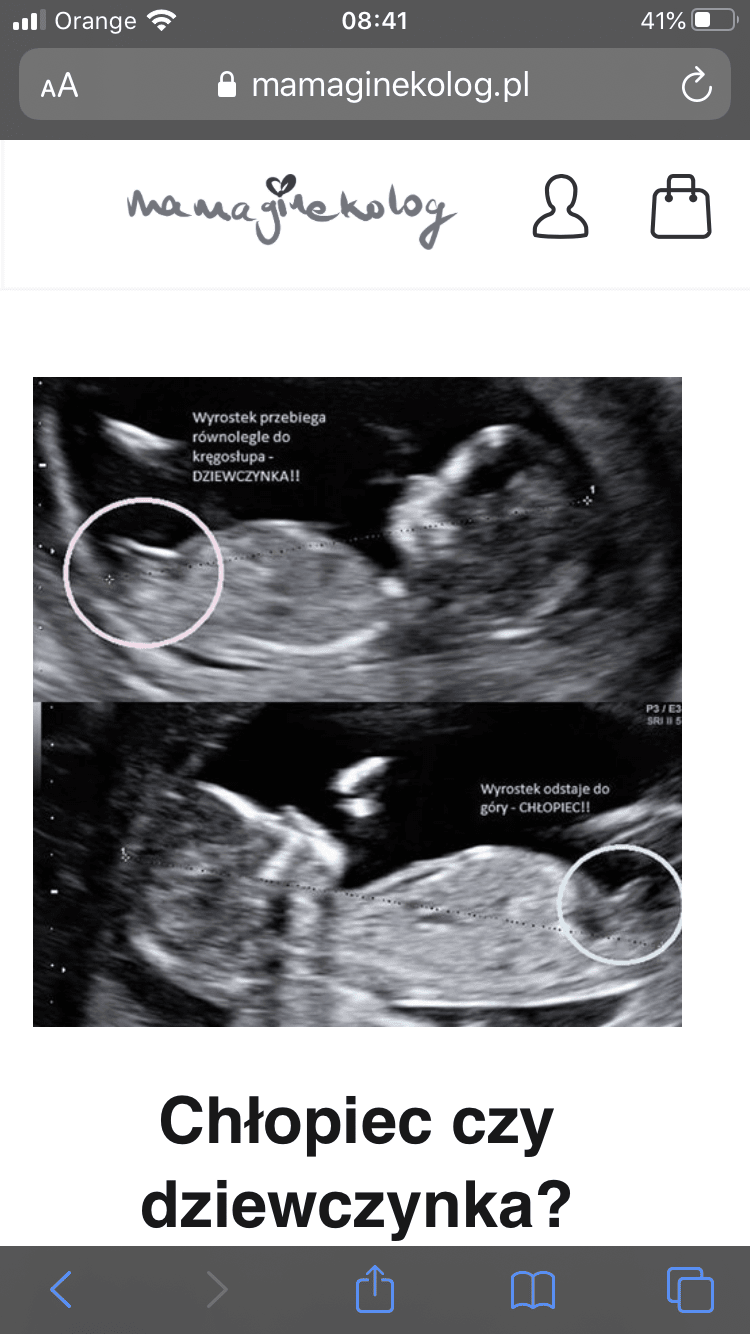

Dziewczyny, a któraś z was oceniała na zdj usg na podstawie wyrostka płciowego jaka to płeć? Lekarz ostatnio nam powiedział, ze on wyraźnie widzi płeć, a my uznaliśmy, żeby poczekać do następnej wizyty, żeby zrobić jeszcze sobie miesiąc niespodzianki :D W środę do lekarza, a ja już chce widzieć :D I tak się przyglądam zdj usg i inf, które znalazłam u mamyginekolog o rozróżnianiu płci.

Załączniki

• 2553DFF5-43EE-4ECB-8049-56F0D9FAC956.png

2553DFF5-43EE-4ECB-8049-56F0D9FAC956.png

155 KB · Wyświetleń: 108